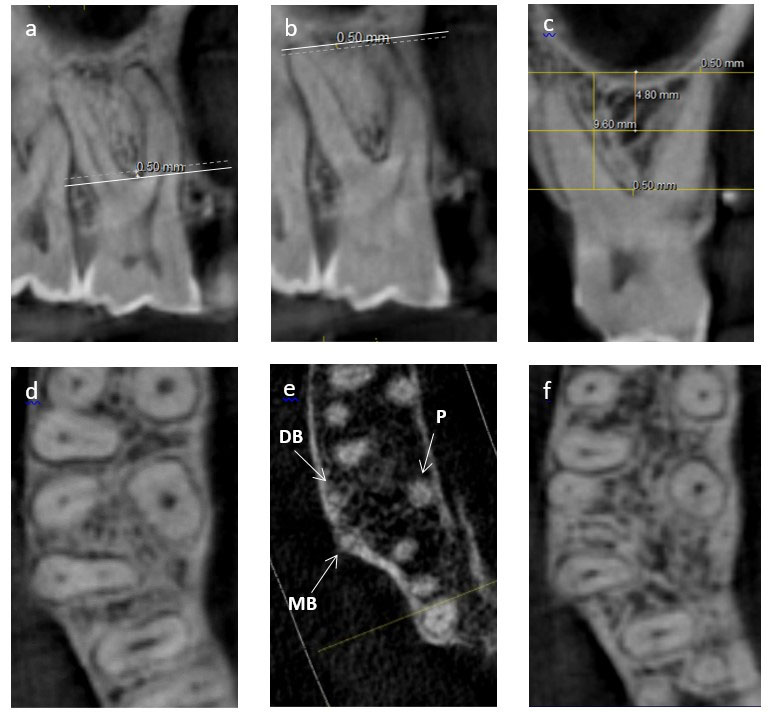

Using axial images, IRS widths were recorded both mesiodistally and buccopalatally at three levels, i.e., crestal widths at 0.5 mm apical to the furcation, apical widths recorded at 0.5 mm coronal to a line connecting the apices of the two shortest roots, and middle level measurements taken at the mid-point between the other two measurement levels (Figure 1).

Figure 1.

(a) A crestal measurement was recorded 0.5 mm apical to the molar furcation. (b) An apical measurement was recorded 0.5 mm coronal to the line connecting the apices of the two shortest roots. (c) A middle measurement was recorded midway between the crestal and apical levels; (d), (e), and (f) show the axial views of the same points corresponding to a, b, and c, respectively (MB: mesiobuccal, DB: distobuccal, P: palatal).